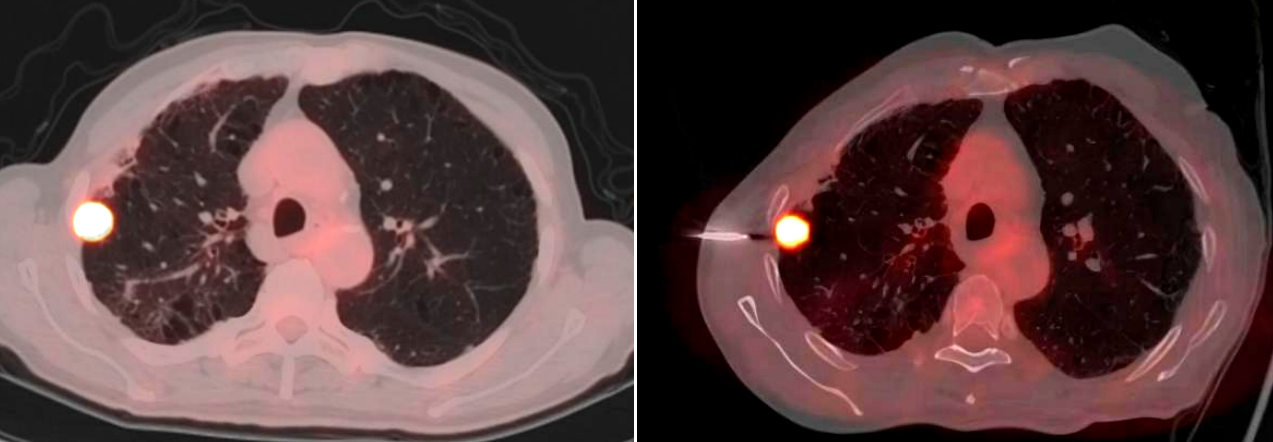

手术当日,PET/CT中心的方龙栋主管技师首先为患者进行了详细的扫描,精准确定了肿瘤的位置和代谢活跃区域。随后,在胸外科医生严密的监测下,精准地将穿刺针经皮穿刺进入患者肺部,准确抵达肿瘤部位,成功获取了病理组织样本。整个手术过程顺利,患者术中及术后均未出现明显并发症。从PET/CT的精准成像,到胸外科医生的穿刺操作,再到病理科的准确诊断,体现了胸外科、PET/CT中心、病理科多学科团队的高效配合和专业能力。

PET/CT中心郝金钢副教授表示,此次云南省首例PET/CT引导下肺肿瘤穿刺活检术的成功开展,标志着医院在肺部疾病影像诊断方面的更进一步。与传统穿刺活检技术相比,PET/CT引导下的穿刺活检具有更高的精准度,能够显著提高病理诊断的阳性率,减少不必要的穿刺次数,降低患者的痛苦和风险。这一技术的应用,将为更多肺部疾病患者带来精准诊断和个性化治疗的希望。

精准定位:PET/CT融合了PET的功能代谢信息和CT的解剖结构信息,不仅能清晰显示肺部结节、占位的形态、大小、位置等解剖特征,还能通过代谢情况准确区分肿瘤组织与周围正常组织、炎性病变等。对于一些在常规CT上难以准确判断边界或性质的微小肺结节、位置特殊的肺占位,通过PET显示病变代谢活性(如SUVmax值),优先选择高代谢区域穿刺,避免坏死组织或炎症干扰,准确到达病变的核心部位,获取更具诊断价值的组织样本,穿刺阳性率可达98.1%,明显减少了常规CT因穿刺误差导致的假阴性(11.7%)。